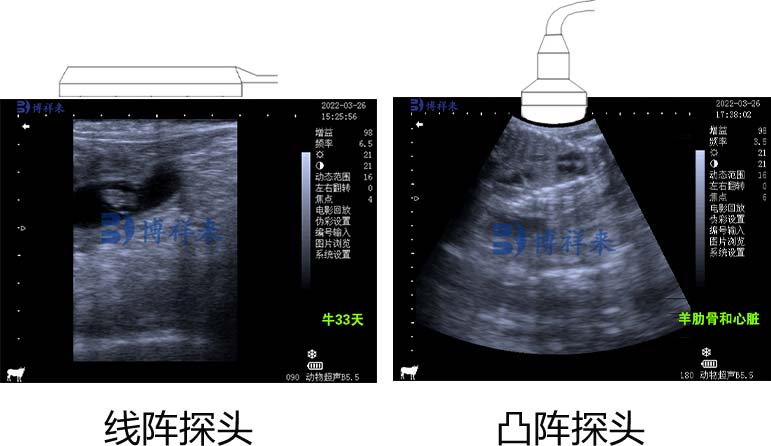

线性扫描探头包含大量晶体,沿着探头的纵轴排列,长度为 5 至 15 厘米。 通过沿着探头顺序激活晶体来对切片进行电子扫描。 线性扫描探头生成矩形图像,该图像具有恒定且足够的宽度以覆盖被检查区域。如果将晶体放置在凸面上,则可以看到更大的区域。 这是凸面或弯曲的线性探头的情况,它生成的图像可能与表面的线性探头产生的图像一样大,但随着图像的深度而扩展。

另外还有一种械扇形探头包含少量旋转晶体、带振荡镜的单晶体或单个振荡晶体。 扇形探头产生一个扇形图像,该图像在表面非常狭窄,并随着深度的增加而扩展。

这使兽医可以查看位于身体深处的大型结构,并通过狭窄的声窗(例如两根肋骨之间的声窗)生成图像。 使用电子扇形探头,晶体会对齐,但生成的图像与使用凸形或弯曲线性探头获得的图像相同。 扇形扫描是通过晶体传输和接收的信号的相位差获得的。 线性扫描探头是牛生殖器官经直肠超声检查的首选,因为它们的形状允许在直肠中进行更安全的操作。 大多数线性探头都有凹槽或指示器,便于在正确定位探头方面进行操作。